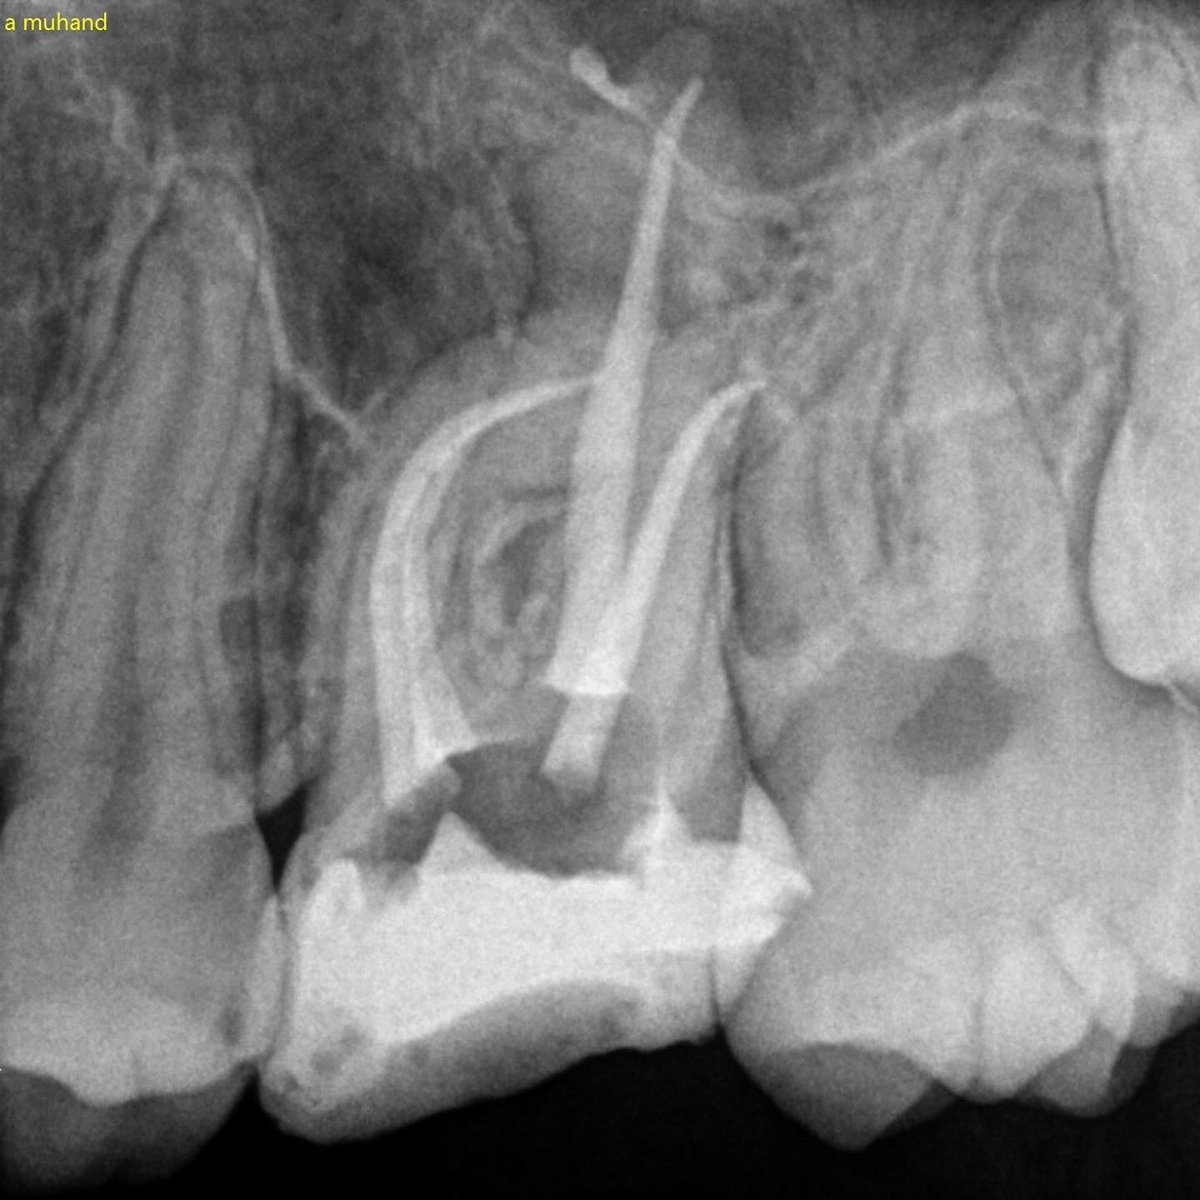

بسم الله نبدأ First endo surgery (Apicoectomy) for tooth #12 Dx: previously treated with symptomatic apical periodontitis + broken file beyond the apex

بسم الله نبدأ

First endo surgery (Apicoectomy) for tooth #12

Dx: previously treated with symptomatic apical periodontitis + broken file beyond the apex